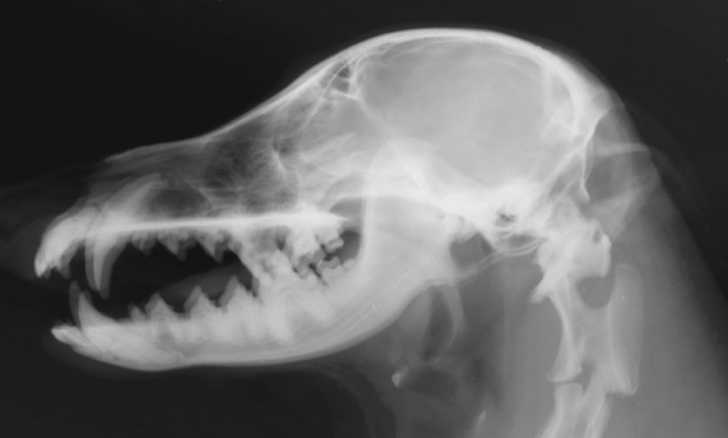

Le scanner permet l'examen des structures intracrâniennes.

Enfin, l'IRM, ou imagerie par résonance magnétique, permet d'obtenir des vues en deux ou trois dimensions de l'intérieur du corps du chien.